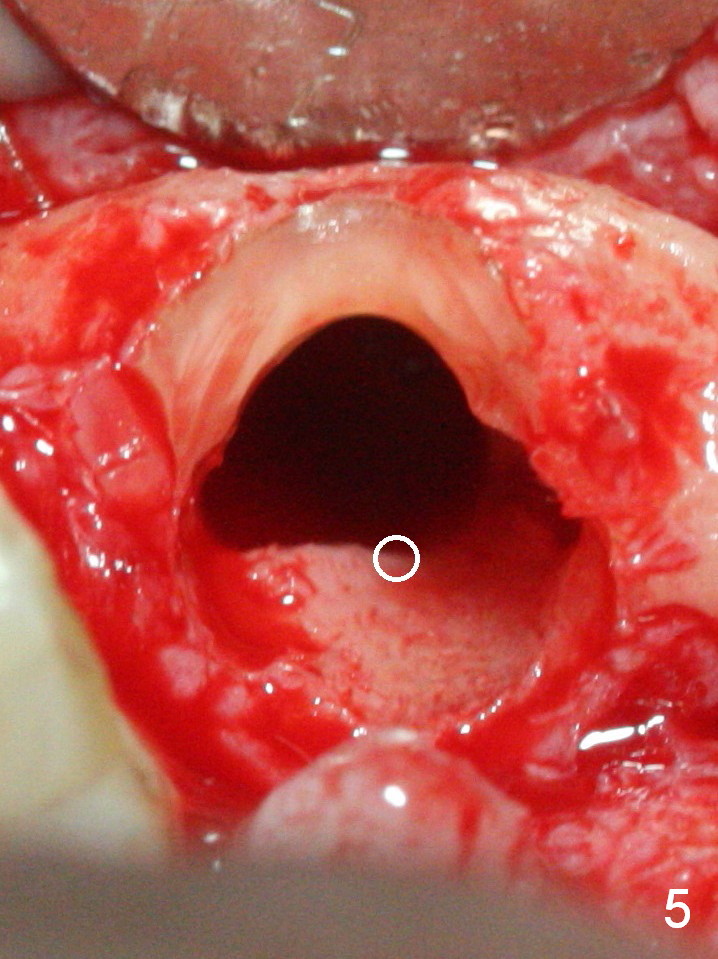

When the bridge is sectioned between #7 and 8, the tooth #6 is found non-salvageable (Fig.1).  Incision shows the atrophic buccal plate at #7 (Fig.2 arrowheads); to prevent the same feature from happening at #6 with thin buccal plate, the most buccal portion of the root is preserved (socket shield (Fig.2-4: *)).  The initial osteotomy is established in the palatal slope at #6 (Fig.5 circle) with 1.5 mm drill (Fig.6,7).  A portion of the root is visible in Fig.6 (arrowheads).  After sequential osteotomy with 2 mm, 3 mm (Fig.8) and 3.2 mm drills, a 4x15 mm implant is placed (Fig.10).  To accommodate the cross bite, the coronal portion of the implant (Fig.9 white circle) is positioned close to the socket shield.  It appears that the shield prevents the implant from encroaching the buccal plate.